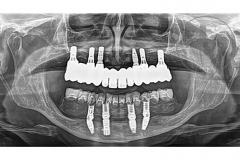

Rehabilitación bimaxilar fija implanto-soportada mediante un enfoque novedoso que se argumenta bajo el uso de nuevos materiales restauradores. Se trata de un paciente que era portador de una rehabilitación sobre implantes previa fracasada. Si desea conocer en detalle las características del caso clínico puede acceder al artículo que publicamos al respecto en el Journal Prosthetic Dentistry